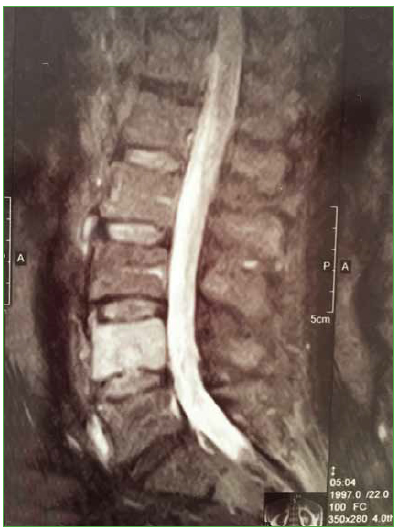

4. Wu HT, Morrison WB, Schweitzer ME. Edematous Schmorl’s nodes on thoracolumbar MR imaging: characteristic patterns and changes over time. Skeletal Radiol 2006;35:212-9. https://doi.org/10.1007/s00256-005-0068-y

13. Hamanishi C, Kawabata T, Yosii T, Tanaka S. Schmorl’s nodes on magnetic resonance imaging. Their incidence and clinical relevance. Spine (Phila Pa 1976) 1994;19:450-3. PMID: 8178234

14. Stabler A, Bellan M, Weiss M, Gartner C, Brossmann J, Reiser MF. MR imaging of enhancing intraosseous disk herniation (Schmorl’s nodes). AJR Am J Roentgenol 1997;168:933-8. https://doi.org/10.2214/ajr.168.4.9124143

15. Jensen MC, Brant-Zawadzki MN, Obuchowski N, Modic MT, Malkasian D, Ross JS. Magnetic resonance imaging of the lumbar spine in people without back pain. N Engl J Med 1994;331:69-73. https://doi.org/10.1056/NEJM199407143310201

16. Takahashi K, Miyazaki T, Ohnari H, Takino T, Tomita K. Schmorl’s nodes and low-back pain. Analysis of magnetic resonance imaging findings in symptomatic and asymptomatic individuals. Eur Spine J 1995;4:56- 9. https://doi.org/10.1007/bf00298420

17. Walters G, Coumas JM, Akins CM, Ragland RL. Magnetic resonance imaging of acute symptomatic Schmorl’s node formation. Pediatr Emerg Care 1991;7:294-6. https://doi.org/10.1097%2F00006565-199110000-00009

18. Seymour R, Williams LA, Rees JI, Lyons K, Lloyd DC. Magnetic resonance imaging of acute intraosseous disc herniation. Clin Radiol 1998;53:363-8. https://doi.org/10.1016/S0009-9260(98)80010-X